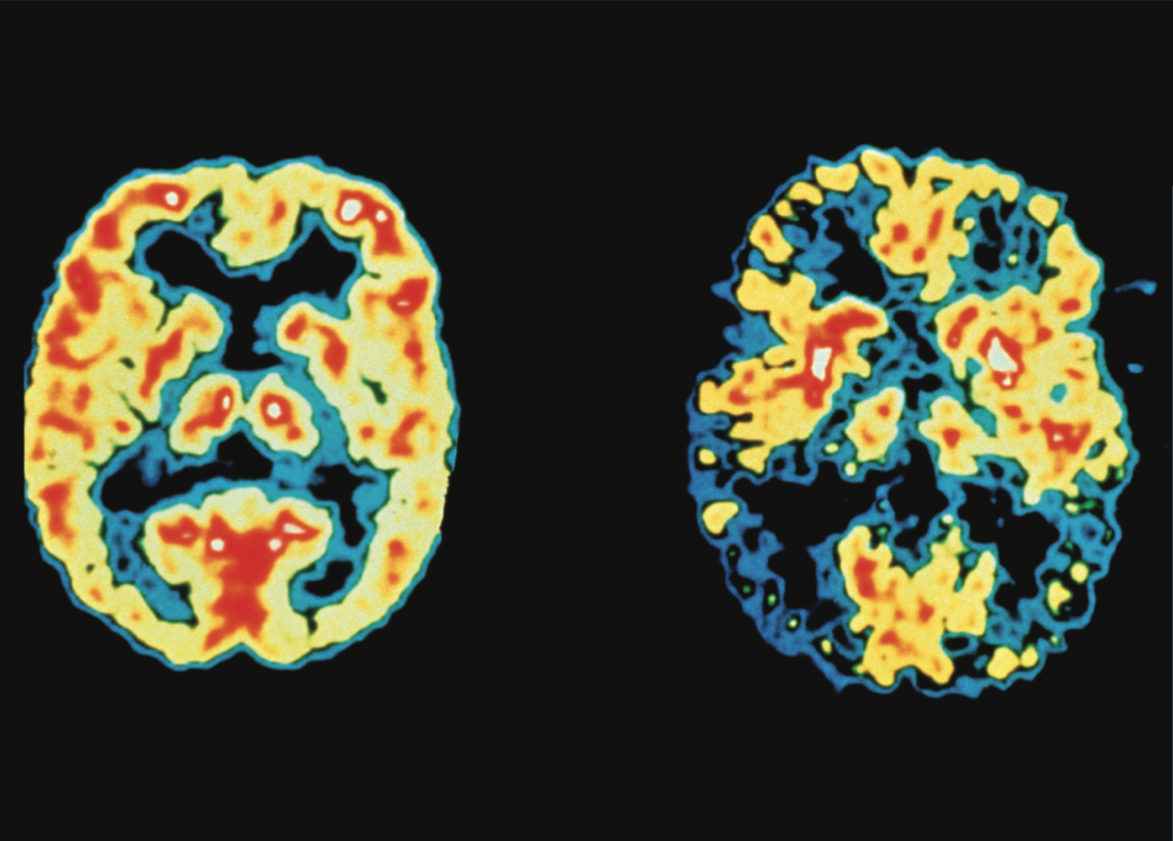

Alzheimer-Demenz

Gedächtnis bei Alzheimer

Alzheimer Pathogenese